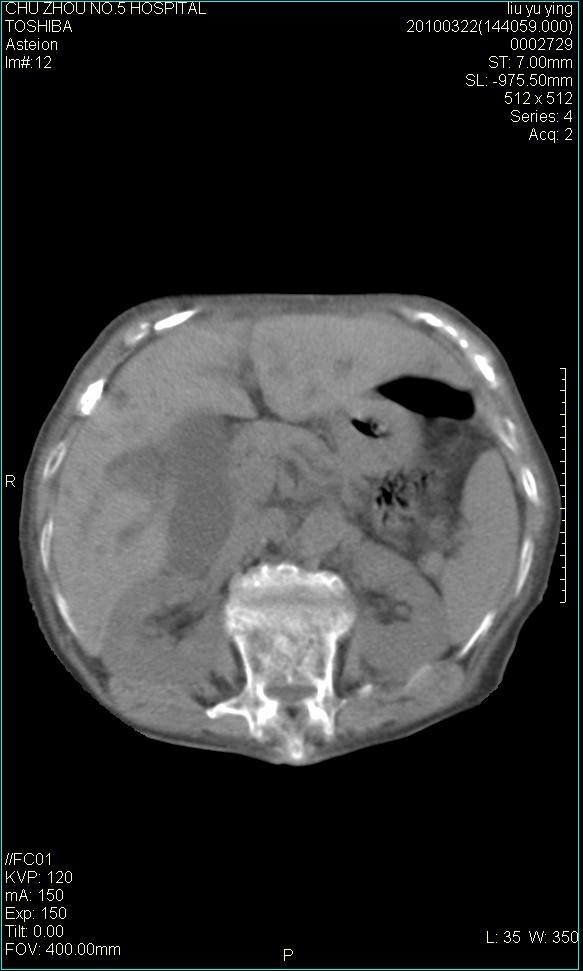

以下是引用科室第一人在2010-3-23 6:50:00的发言:[br]胆总管下段梗阻,多为肿瘤性病变,巨形胆囊,胆囊炎胆囊窝积液。[br]双侧胸腔积液,右降

以下是引用随光逐影在2010-3-23 8:12:00的发言:[br]1)胆系低位梗阻(肝内外胆管扩张,胆囊增大),原因待查。2)胆囊炎。3)双侧少量胸腔积液。4)降主动脉迂曲。